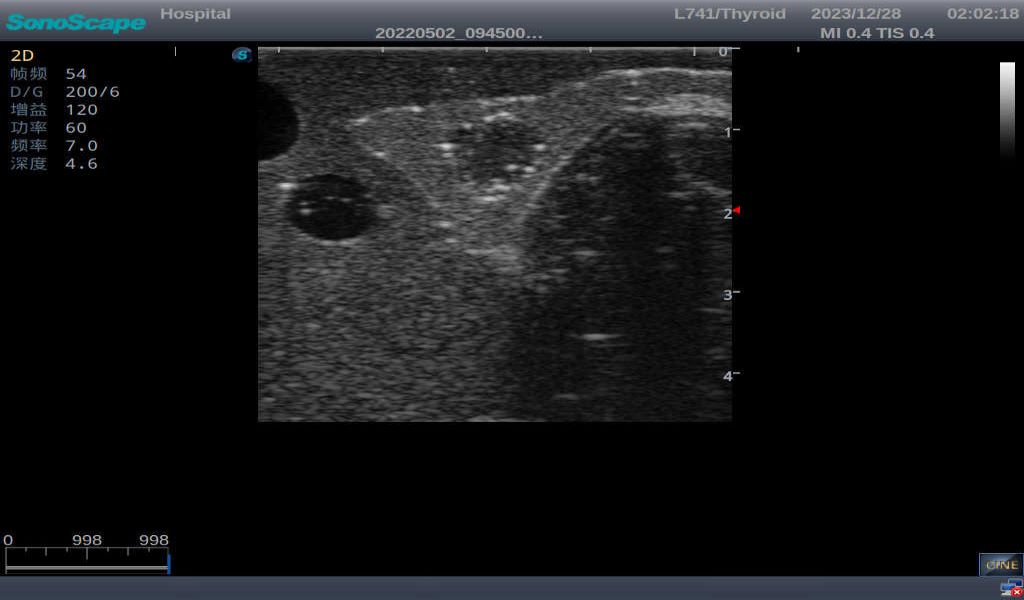

3)       It comes with four (4) thyroid modules and can show five (5) ultrasonic images: normal thyroid, thyroid adenoma, thyroid cancer, nodular goiter, thyroid cyst

Thyroid adenoma with well-defined border and smooth uniform halo